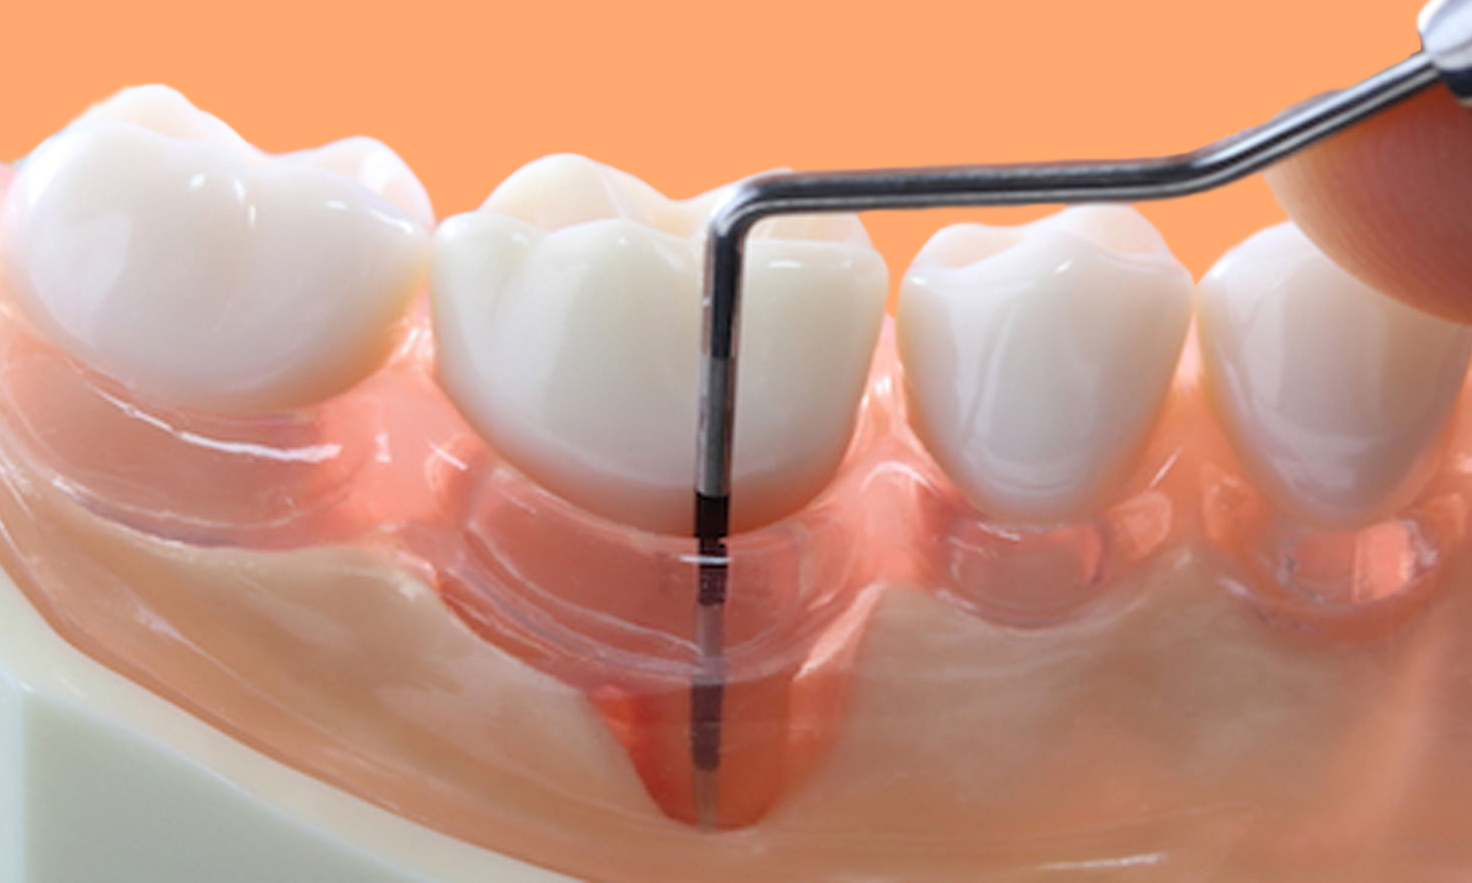

A periodontite agressiva juvenil, quando não tratada, pode trazer sérias consequências para a saúde bucal. Por isso, a limpeza profissional não é só um cuidado estético, é a base para o controle dessa condição. Dentistas e higienistas têm as ferramentas e o conhecimento para remover aquela placa bacteriana e o tártaro que o dia a dia em casa não alcança. É um passo fundamental para frear a progressão da doença.

Nesse tratamento, o foco é a remoção minuciosa das bactérias. Os profissionais utilizam instrumentos específicos para limpar profundamente as bolsas periodontais, que são aquelas espaços que se formam entre o dente e a gengiva quando a doença avança. O objetivo é criar um ambiente bucal mais saudável, onde a gengiva possa começar a se recuperar e a inflamação diminua. É um trabalho delicado, que exige precisão.

Se você ou alguém que você conhece está lidando com periodontite agressiva juvenil, saiba que existem caminhos eficazes para o tratamento. A primeira linha de ataque geralmente envolve procedimentos feitos no consultório do dentista. São eles que vão limpar profundamente as bolsas periodontais, removendo o máximo possível da bactéria que causa o problema. Isso é crucial para frear a progressão da doença.

A regeneração tecidual entra em cena depois que a inflamação está sob controle. O objetivo é recuperar os tecidos que foram danificados pela doença. Isso pode envolver procedimentos como raspagem e alisamento radicular para limpar as bolsas periodontais. Em casos mais avançados, a gente pode pensar em enxertos ósseos ou de gengiva, tudo para ajudar o corpo a se reconstruir.